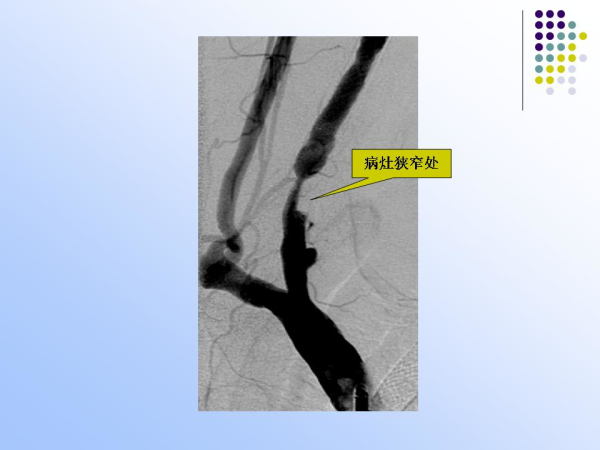

【治疗脑血管病的新技术:血管内介入治疗】—神经内科脑卒中筛查与防治办公室

神经内科

脑卒中筛查与防治办公室